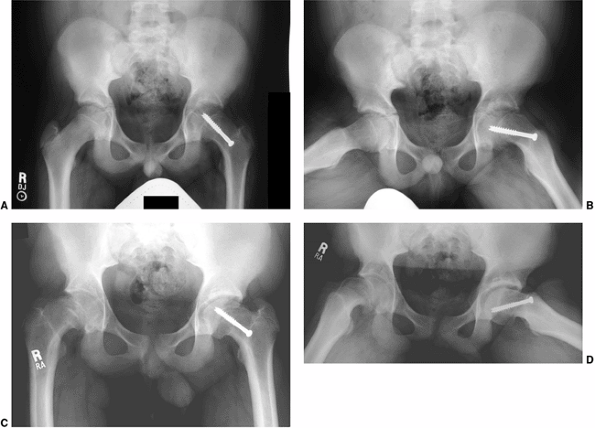

Physeal widening, osseous edema adjacent to the physis, and the

anatomic deformity associated with SCFE are typically seen, with the

findings of physeal widening and irregularity as well as osseous edema

adjacent to the physis seen in cases of “pre-slips” (125). In a child with suspected SCFE and normal radiographs, MRI is useful in determining whether a pre-slip is present (Fig. 26.2). Currently, MRI scanning is rarely used in evaluating patients with evident SCFE.

Figure 26.2

A 12-year-old boy presented with pain in the right hip for two months. On further questioning, he reported some vague, intermittent symptoms in the left hip. Physical examination revealed pain in the right hip and obligate external rotation, but no such findings on the left. A, B: Anteroposterior and frog pelvis views at the time of presentation. A right slipped capital femoral epiphysis (SCFE) is evident, without definite plain radiographic changes on the left. C, D: Because of the vague left hip symptoms, magnetic resonance imaging (MRI) was done to rule out a left SCFE. MRI demonstrated physeal widening and irregularity (T1: flip angle 90, TR 700, TE 18) (seen best in C) and signal change on the right, mostly in the metaphysis in this case (fat saturation: flip angle 90, TR 4500, TE 75.37) (best seen in D), without any definite abnormalities on the left. Only the right hip underwent in situ fixation because of the normal physical examination and the lack of considerable MRI findings in the left hip. The patient denied ongoing pain in the left hip until nine months following in situ pinning of the right hip. He then had progressive pain in the left hip and re-presented to the orthopaedist one month later, at which time a mild left SCFE was noted and in situ fixation of the left hip was performed. |